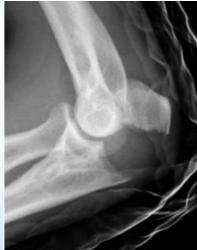

Injection for Tennis elbow (Lateral Epicondylitis)

This patient has lateral epicondylitis. You are required to give him an injection

| Site of injection | Lateral epicondyle: → Common extensur |

| Ο Feel and identify area of maximum tenderness | |

| Ο Just distal to tip of lateral epicondyle | |

| Injection | Needle perpendicular to skin |

| Ο If at proper site, the green light should turn on | |